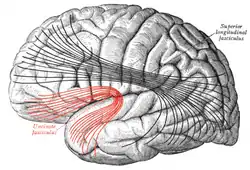

![]() Lateral surface of left cerebral hemisphere. Some of the major association tracts are depicted. Uncinate fasciculus is at lower left, in red. | |

Diagram showing principal systems of association fibers in the cerebrum. (Uncinate fasc. visible at lower left, in red.)